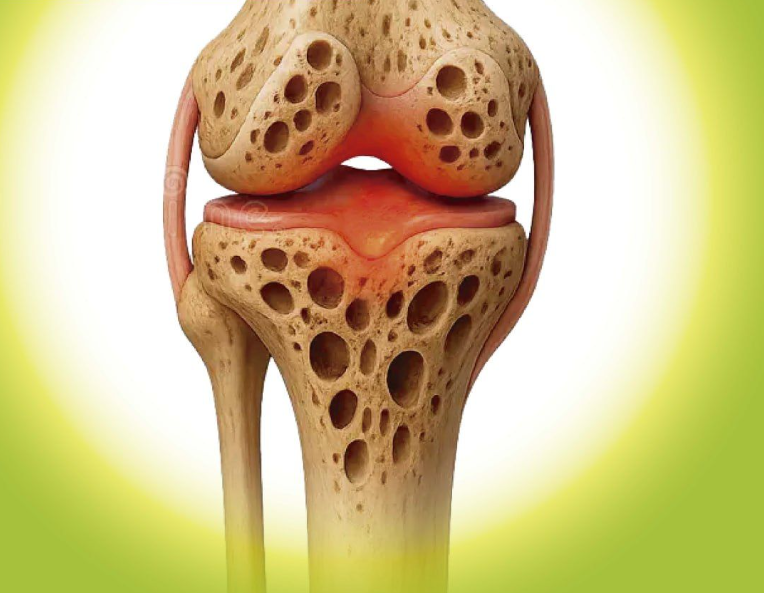

Knee joints are remarkable structures. They allow us to walk, squat, climb, and move freely by relying on a smooth layer of cartilage that cushions the bones and absorbs shock. However, cartilage is not static—it’s constantly being broken down and rebuilt.

A 2024 study published in the journal Osteoarthritis and Cartilage reported that collagen breakdown accelerates with age, contributing to common joint changes seen in older adults. Collagen is the primary structural protein in cartilage, and when the body produces less of it, cartilage may gradually thin.